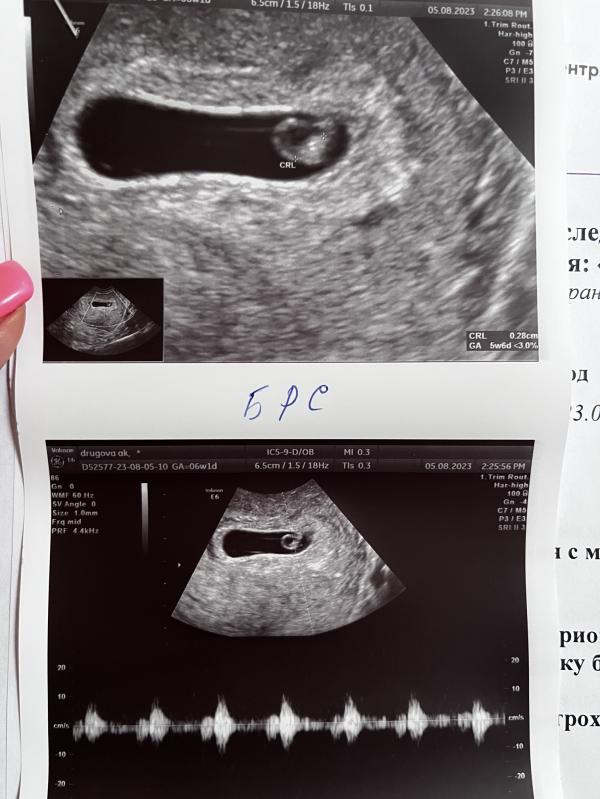

Сходила на узи сегодня,и обрадовалась и расстроилась🫣

Сегодня увидели и даже услышали сердечко маленькой креветки😍растет)ктр 2,8 мм

Срок поставили 5,6 🌺

Но ещё увидели ретрохориальную гематому 12х5 мм.